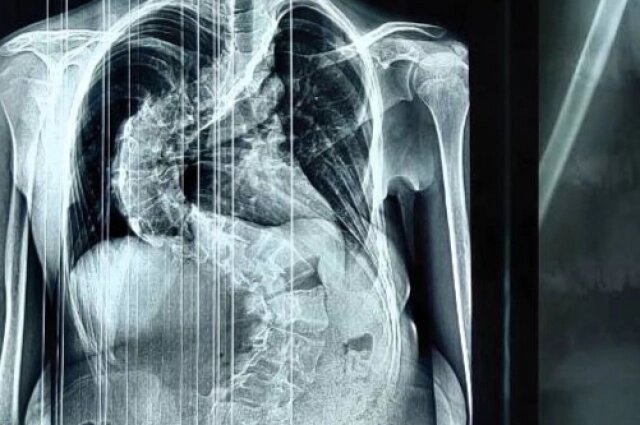

Как рассказал заведующий детским травматолого-ортопедическим отделением Алексей Молчанов, пациентке диагностирован диспластический s-образный грудопоясничный сколиоз 4 степени.

Фото: Министерство здравоохранения Кировской области

«Несмотря на молодой возраст, тяжёлая, ригидная деформация уже сформировалась. Позвоночник девочки был сильно деформирован и по форме напоминал латинскую букву S. При наклоне туловища вперёд в грудном отделе справа определялся пологий рёберный горб, правое надплечье было выше левого на 2 см», — рассказал врач.

По словам Алексея Молчанова, сколиоз такой тяжёлой формы вызывает множество изменений в организме и приводит к необратимым последствиям для дыхательной, сердечной и других важнейших функций организма. Страдают внутренние органы. В том числе жизненно важные.

«Позвоночник девочки был сильно деформирован. Деформация сжала левое лёгкое, сердце сместилось в правую сторону. Сколиоз такой тяжёлой формы мог привести к необратимым последствиям для дыхательной, сердечной и других важнейших функций организма. Оперативное вмешательство было жизненно необходимо», — пояснил Алексей Молчанов.